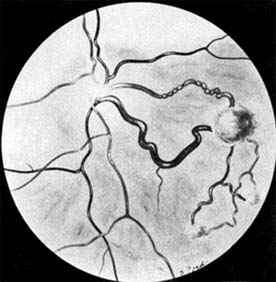

Retinal hemangiomas occur as isolated tumors or associated with cerebellar hemangioblastomas, pancreatic cysts and carcinomas, renal cysts and carcinomas, and pheochromocytomas in von Hippel-Lindau syndrome (Figure 10-30). The retinal tumors are pink or red, endophytic, and usually supplied by a large feeder vessel. Juxtapapillary tumors are usually exophytic. Vision is affected by bleeding or exudation from the tumor vessels. Photocoagulation, diathermy, and cryotherapy are used to treat the retinal lesions.

Figure 10-30

Figure 10-30: Angiomatosis retinae of Von Hippel-Lindau disease (drawing). (Courtesy of F Cordes.)